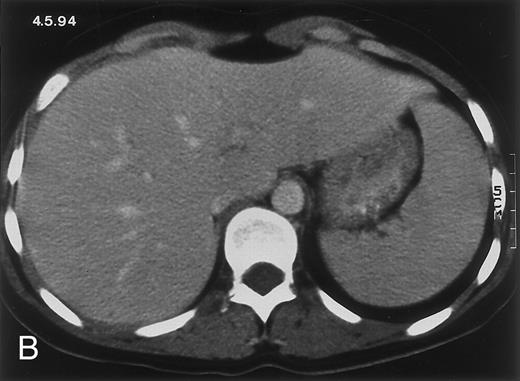

Radiologic evolution in patient B. (A) Postcontrast abdominal CT scan on February 10, 1994 shows multiple small hypodense areas in all segments of the liver suggestive of hepatic candidiasis. Twenty-four days previously, the patient had recovered from severe neutropenia after the second cycle of chemotherapy for ALL. (B) On May 4, 16 days after the neutrophil count had dropped below 500/μL in the third chemotherapy cycle, there is clear improvement of the radiologic findings, with only a few hypodense areas in the liver.